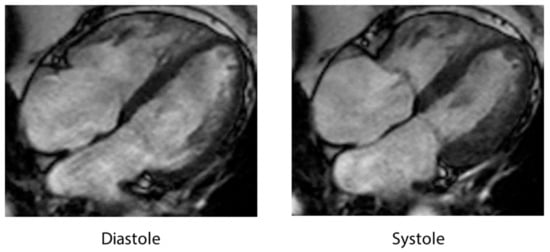

4.5. Cardiac Magnetic Resonance Imaging

| CMR (cardiac magnetic resonance) | RWMAs, RV involvement, late gadolinium-enhancement signal intensity threshold < 5 SD, and edema using T2 weighted imaging in dysfunctional LV regions. |